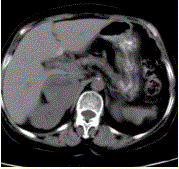

问题 患者男,41岁,发作性头晕、恶心、面色苍白伴高血压半年,入院观察,当时测血压180/80mmHg;上腹部CT示:右侧肾上腺区有直径为5cm圆形稍高密度影,边界清晰,内部密度不均(下图)。 根据病史和影像学表现,患者最可能的诊断为

选项 A.肾上腺囊肿 B.肾上腺转移瘤 C.肾上腺髓样脂肪瘤 D.嗜铬细胞瘤 E.肾上腺腺瘤

答案 D